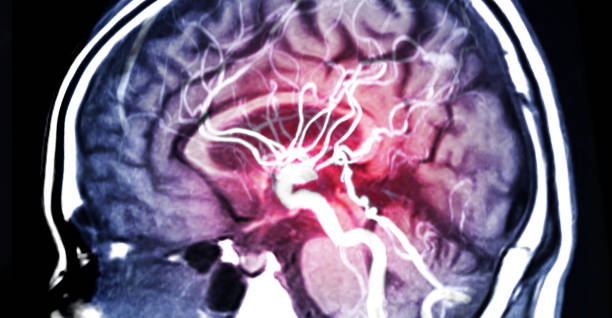

뇌출혈은 두 개 내에 출혈이 있어 생기는 모든 변화를 말하는 것으로 가장 큰 원인으로는 고혈압 증상을 지목하곤 합니다. 고혈압은 산소와 영양소가 뇌로 들어가는 통로인 혈관에서 변화를 일으키기 때문인데 뇌동맥류가 손상된 경우에도 발생할 수 있으며 잦은 흡연이나 음주 등 여러 원인으로 합병증으로 인해 발생할 수 있습니다. 특히, 뇌출혈 증상 발생시 가능한 빨리 병원으로 가야하고 약 2시간 안에 응급처치를 받아야 하는데 이는 응급처치를 받지 않으면 바로 뇌 손상으로 사망에 이를 수 있기 때문에 이번 시간에는 뇌출혈 전조증상에 대해 정리해 보겠습니다.